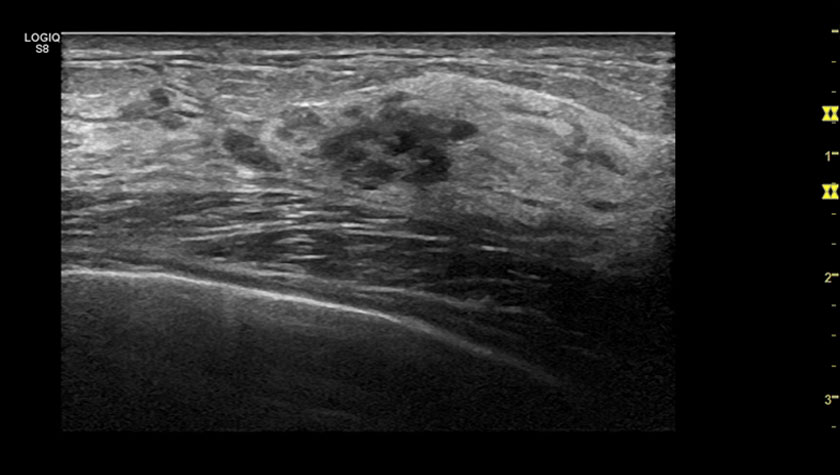

Щитовидная железа, 2D-эластография сдвиговой волны

Щитовидная железа, датчик L3-12-D

Молочная железа, датчик ML6-15-D

Эластография молочной железы, датчик ML-6-15-D